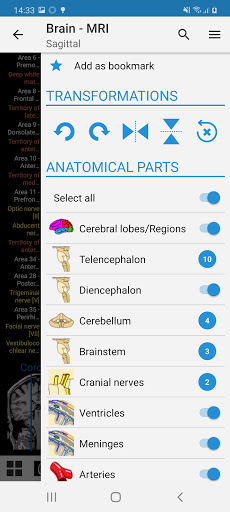

- Pilih label anatomi berdasarkan kategori

e-Anatomy memiliki lebih dari 26.000 gambar yang berisi serangkaian gambar dalam tampilan aksial, koronal, dan sagital serta radiografi, angiografi, gambar diseksi, bagan anatomi, dan ilustrasi. Semua gambar medis diberi label dengan cermat, lebih dari 967.000 label tersedia dalam 12 bahasa termasuk Terminologia Anatomica Latin.